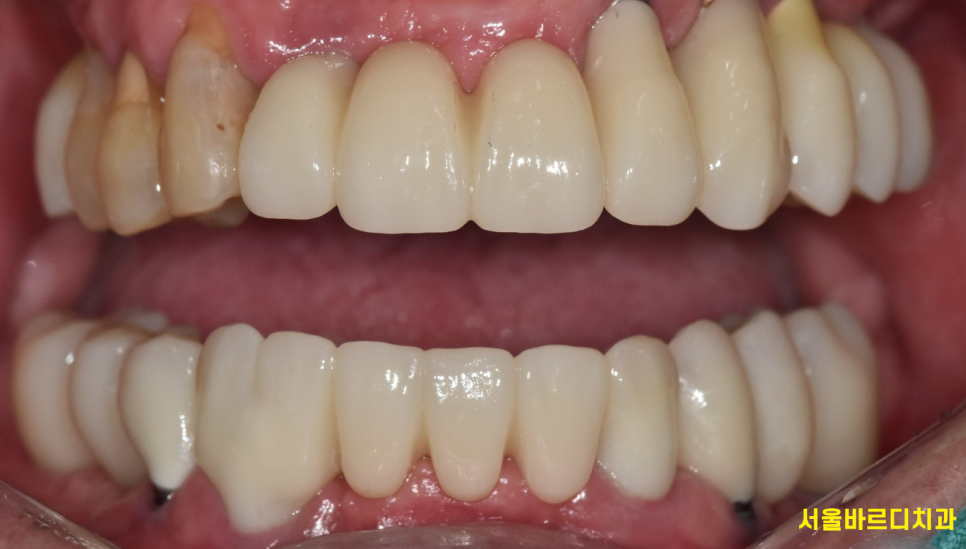

241120

앞니와 어금니 동시에 완성해드린 사진입니다.

250103

치료 순서도 만족하고

환자분의 요구사항도 반영한 케이스였습니다.

어금니도 올바르게 들어갔기 떄문에

앞니에 무리한 힘을 줄 일도 없고요~~